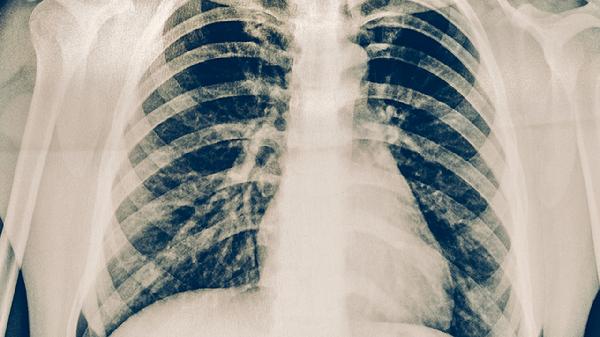

與活動性肺結(jié)核患者共同生活或工作,長期處于密閉環(huán)境且通風不良時,通過飛沫傳播感染概率顯著增加。接觸者可能出現(xiàn)咳嗽、胸痛等呼吸道癥狀,建議進行胸部X線檢查。預防措施包括佩戴口罩、保持通風,接觸后可使用吡嗪酰胺片等藥物預防性治療。